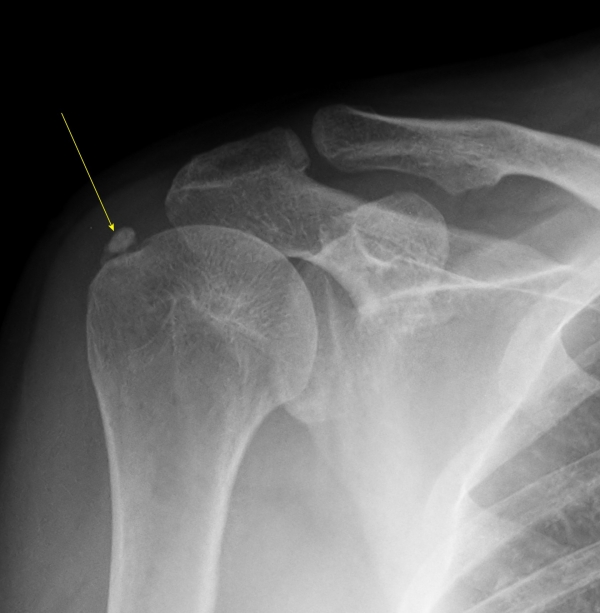

¹æ»ç¼± °Ë»ç :  1Â÷ ¹æ»ç¼± °Ë»ç¿¡¼­ ±Ø»ó°Ç³» °íÀ½¿µ ¼®È¸°¡ °üÂûµÊ(»çÁø 5).

2Â÷(¾à 1°³¿ù ÈÄ) ¹æ»ç¼± °Ë»ç¿¡¼­ ¼®È¸°¡ °üÂûµÇÁö ¾ÊÀ½(»çÁø 6).